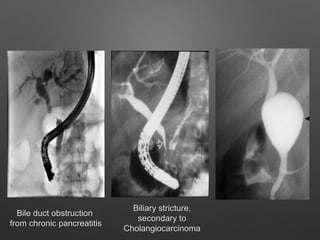

Bile duct obstruction

from chronic pancreatitis

Biliary stricture,

secondary to

Cholangiocarcinoma